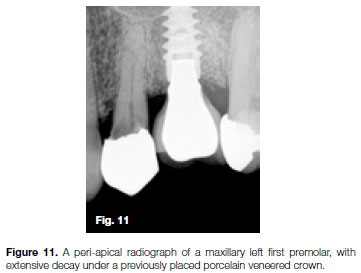

The patient, a 54 year old female, presented with irreversible pulpitis on her maxillary left first premolar, caused by extensive decay under a previously placed porcelain veneered crown (Figure 11). After removal of the defective crown and decay a core build-up was done prior to root canal treatment. A size 10 K-File was negotiated to full working length and confirmed radiographically (Figure 12). Note the sharp apical curvature in the last 3mm of the root canal system.